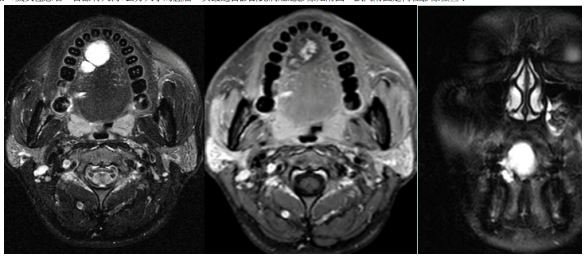

68.26歲女性患者,舌部有大約3公分大小的腫瘤,其最適合診斷此病灶之影像如附圖,試問附圖是何種影像檢查?

(A)CT scan (B)MRI (C)Tomography (D)Ultrasound